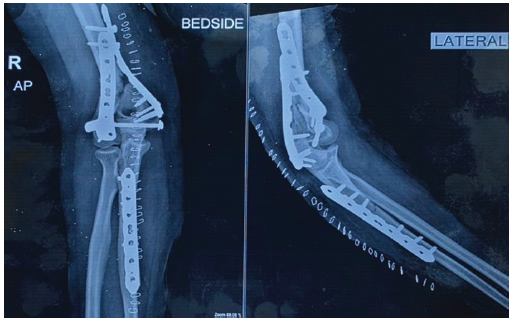

The patient was followed over a 6 months period following completion of PRP therapy. She attended monthly outpatient visits where pain, range of motion, and radiographic healing were assessed. At 1 month post-treatment, she reported reduced pain and improved use of the arm, although imaging showed no significant change at the fracture site. Despite this, she resumed light household tasks and was able to use the arm for basic activities without major discomfort. By the 3rd month, she demonstrated progressive improvement in function. At 4 months, radiographs revealed visible bridging callus across the distal humerus (Fig. 5), and by 6 months, cortical continuity was seen, confirming radiological union (Fig. 6).

Figure 5: Four-month post-platelet-rich plasma anteroposterior and lateral radiographs showing early bridging callus formation at the distal humerus fracture site with stable fixation in situ.

Figure 6: Six-month post-platelet-rich plasma anteroposterior and lateral radiographs demonstrating cortical continuity and radiological union of the distal humerus with stable fixation in situ.